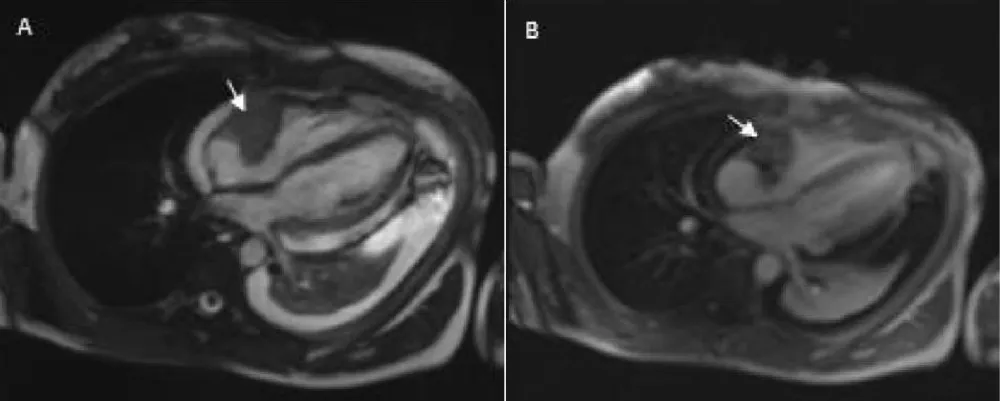

To better delineate and characterize the cardiac mass, a chest CT was performed (Figure 1). This examination revealed moderate pericardial effusion with the existence of a low attenuation mass in the right atrium, extending along the pericardium with heterogeneous enhancement, of approximately 3.5 cm, which corresponds to a cardiac tumor. Cardiac magnetic resonance imaging (Figure 2) exposed a cardiac mass at the level of the right atrium with extension into the pericardium and free wall of the right ventricle and heterogeneous late enhancement, being hypointense on T1 and T2, This is not the most typical pattern, which usually consists of low signal T1-weighted sequences, and increased signal and central areas of hyperintensity on T2weighted, consistent with hemorrhage and necrosis, and areas of moderate signal intensity in more peripheral regions [3]. Because of their high vascularity, strong signal enhancement is seen after the administration of IV gadolinium [3]. However, given the propensity of angiosarcomas to necrosis and hemorrhage, these often have heterogeneous signals on cardiac MR images [3]. Fluorodeoxyglucose-18 combined with positron emission tomography/computed tomography (18F-FDG-PET/CT) (Figure 3) confirmed pathological metabolic activity in the recognized mass in the right atrium extending along the pericardium with intensely increased FDG uptake (SUVmax) of 17.3. Moderate Pericardial effusion was noted and multiple hypermetabolic foci in the bodies of the D12, L2, and L3 vertebrae, as well as in the proximal third of both femurs, without evidence of structural lesions on CT with SUVmax of 6.9.

Download Image

Figure 2: Cardiac MRI findings: A: Axial T2-weighted images mass in the right atrium hypointense on T2 with extension into the pericardium and free wall of the right ventricle (arrow) B: Axial T1weighted image after administration of gadolinium shows heterogeneous late enhancement of the right atrial mass (arrow).